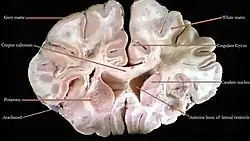

Creierul uman | |

Secțiune a creierului uman | |

Anatomie

Creierul este format din trei părți principale: anterioară, medie și posterioară.